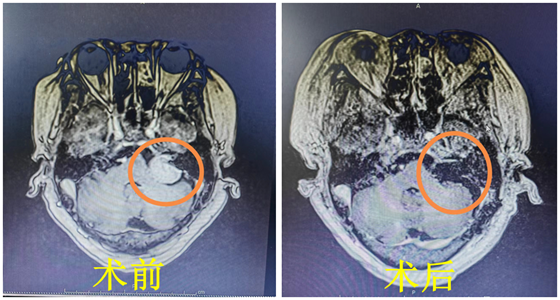

近日,70岁的广东省朱大爷在湘雅常德医院接受了听神经瘤切除手术,这是医院自建院以来,神经外科全国知名教授、湘雅常德医院神经外科主任袁贤瑞为第200位患者成功实施的听神经瘤全切...